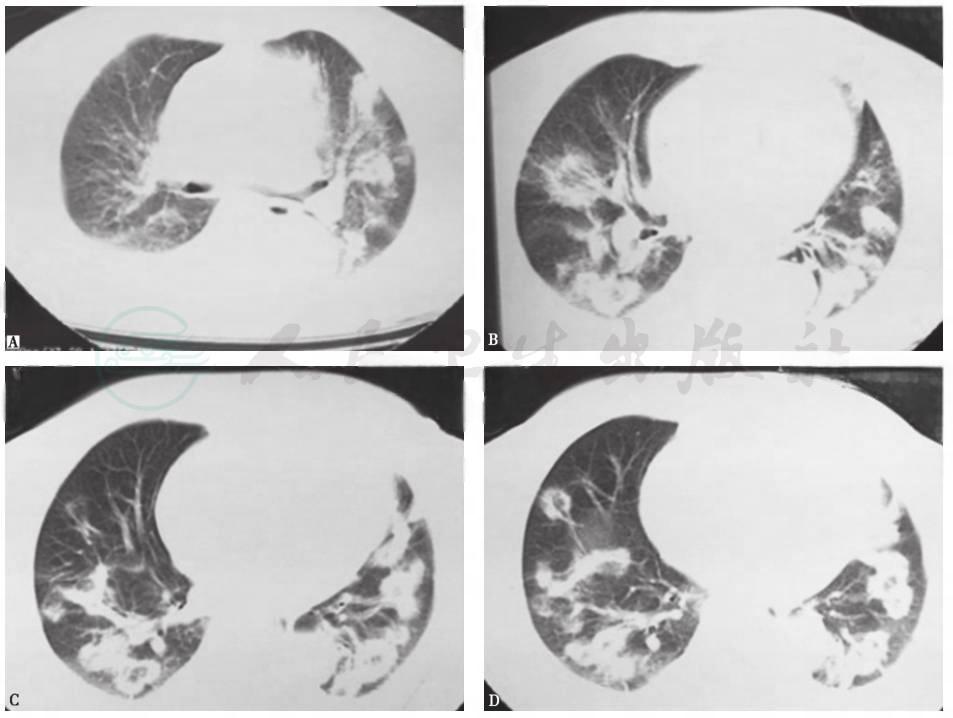

患者经口服糖皮质激素抗炎治疗后稳定恢复,复查胸部CT见图10~图12。

图10治疗8天时胸部CT表现

胸部CT见双肺原有病灶明显吸收,胸腔积液消失

图11治疗22天时胸部CT表现

胸部CT见双肺原有病灶明显吸收,部分病灶完全吸收

图12治疗3个月时胸部CT表现

胸部CT见双肺原有病灶完全吸收消失

通过一系列经验的、循证的临床证据分析,患者肺内病变的性质诊断为隐源性机化性肺炎(COP),这也可解释为何经验性抗感染治疗无效。COP是一组原因不明的少见疾病。其相应的临床-放射-病理学定义为在没有明确致病原(如感染)或其他临床伴随疾病(如结缔组织疾病)情况下出现的机化性肺炎,大多对糖皮质激素治疗有较好反应。COP发病率男女基本相等,发病年龄多在50~60岁,与吸烟无明显相关性。其临床表现缺乏特异性,常为亚急性起病,病程较短(中位病期<3个月),常见临床症状为发热、刺激性咳嗽、乏力,伴体重下降、厌食及胸闷等不适,咯血、夜间盗汗、气胸、纵隔气肿及关节肌肉疼痛少见,气短的症状较轻,上述临床症状可在数周内进展。体检时可发现局限性或广泛性的湿啰音和/或Velcro啰音,多位于两肺中下部,部分患者亦可无任何体征表现。常规实验室检查无特异。肺功能主要表现为轻至中度限制性通气障碍。大多数患者胸部影像学检查可有异常发现,且具有“五多一少”的特点,即多态性、多发性、多变性、多复发性、多双肺受累(图13),蜂窝肺少见。COP的主要病理变化是呼吸性细支气管及以下小气道和肺泡腔内有机化性肺炎改变,病变表现单一,时相一致,呈斑片状和支气管周围分布,位于气腔内,肺结构没有破坏。

图13隐源性机化性肺炎胸部CT表现

女性患者,64岁,咳嗽、间断发热4个月余。胸部CT见右肺多叶段高密度实变影,右下肺膨胀不全伴轻度反晕征